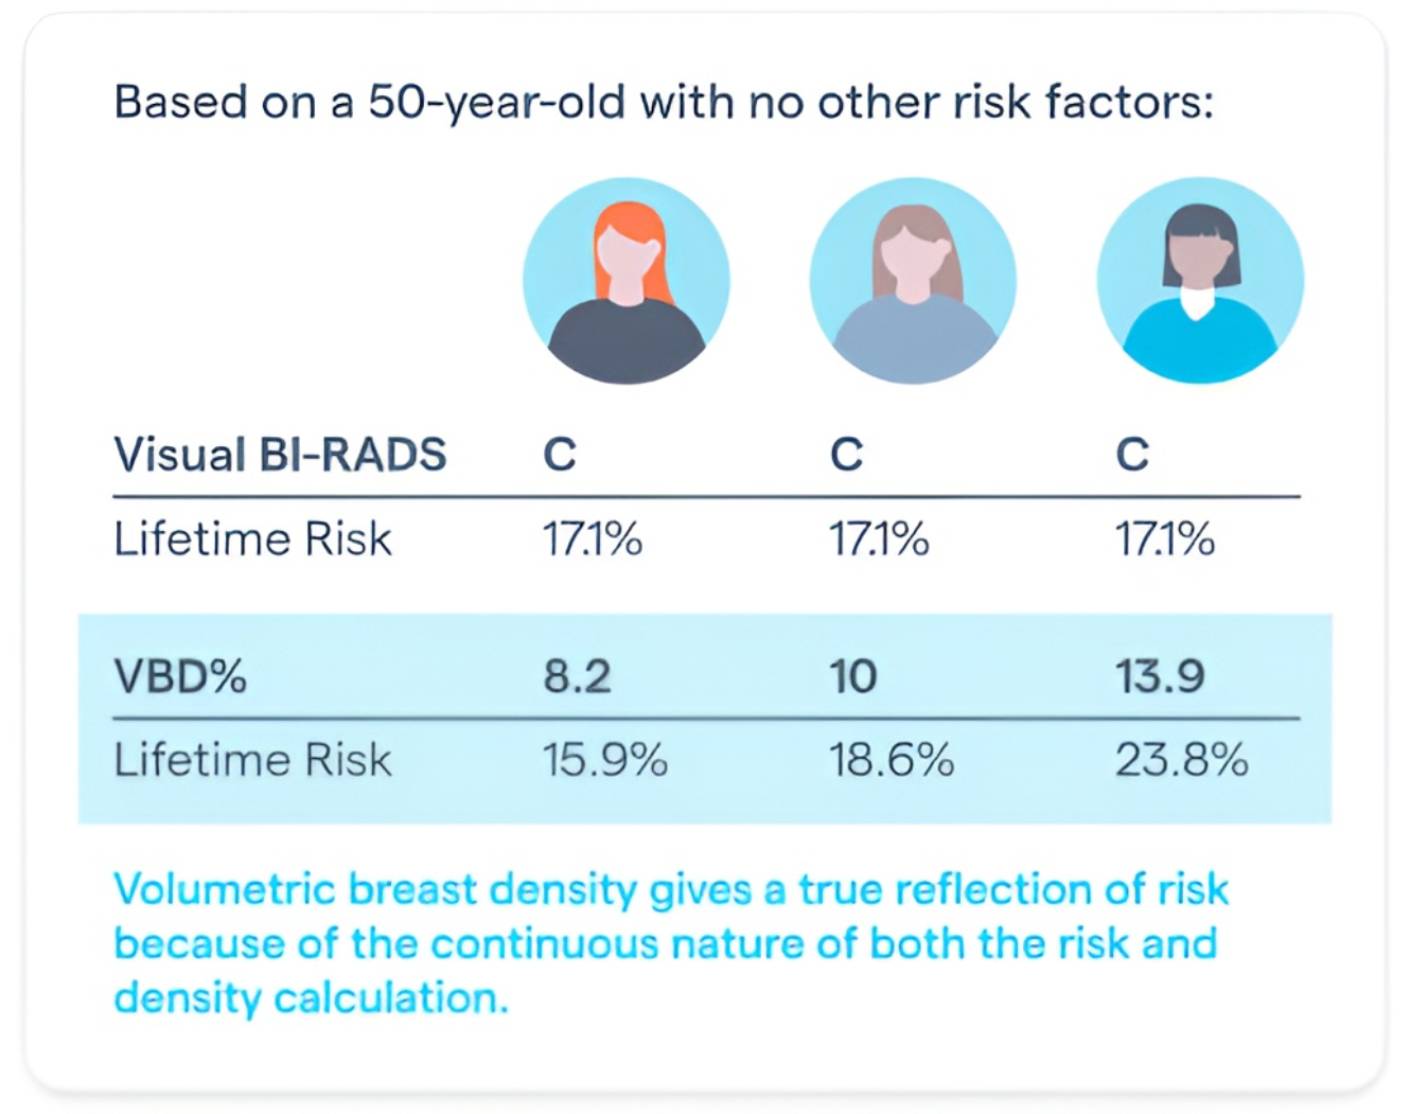

When input to the TC8 model Volpara has been shown to change the risk of 4.5%* of patients.

*Destounis, S. V., et al. (2021, November–December). Impact on risk categorization with inclusion of mammographic density in the Tyrer-Cuzick model. Abstract presented at the Radiological Society of North America (RSNA) 107th Scientific Assembly and Annual Meeting, Chicago, IL.

As the only breast density assessment software validated for use with Tyrer-Cuzick v8 (TC8), it provides precise data to support lifetime breast cancer risk assessment to help identify patients who may need additional imaging or preventive measures.

By providing an objective density score, we help clinicians determine when supplemental screening methods may be necessary, ensuring that high-risk patients receive the right care at the right time.